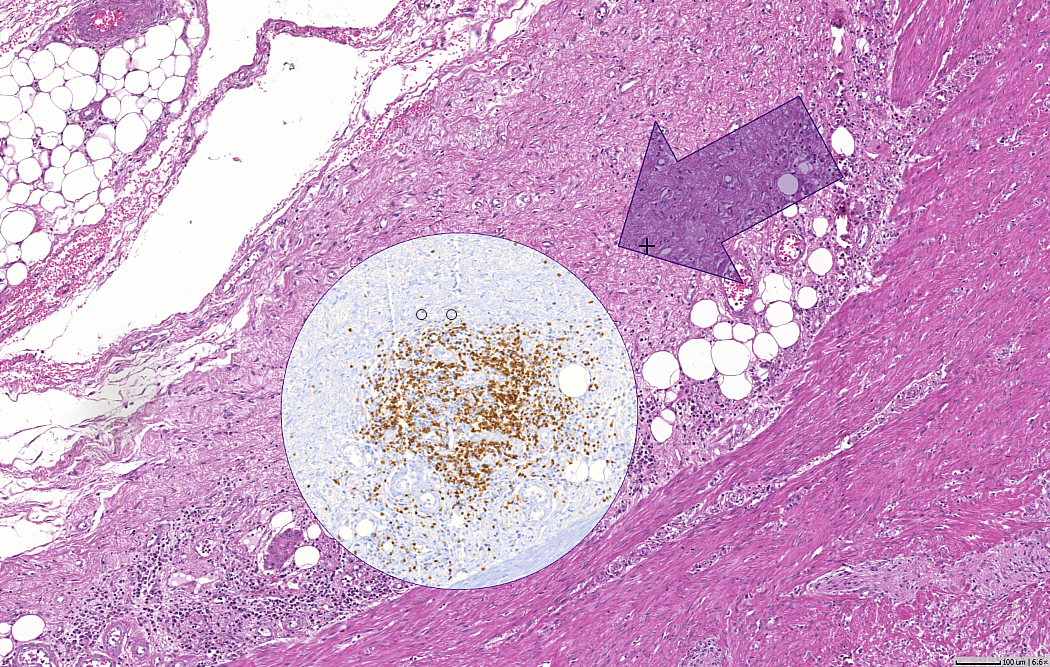

during the discussions at ECDP 2016 in Berlin it turned out that working with multiple slides of the same tissue in different IHC stainings is becoming more and more interesting. Analyzing differently stained sections can be particularly useful in applications such as tumor score computation, biomarker development, or companion diagnostics.

In order to perform analysis on multiple stains efficiently, the digital slides need to be accurately aligned. Our software Slidematch is a powerful and easy to use tool to automate this alignment process. It enables batch processing of up to 25 slides in one go and accurately aligns the images on all magnification levels up to the scan resolution. The aligned images can then be viewed, analyzed and annotated with our free digital pathology viewer Zoom.